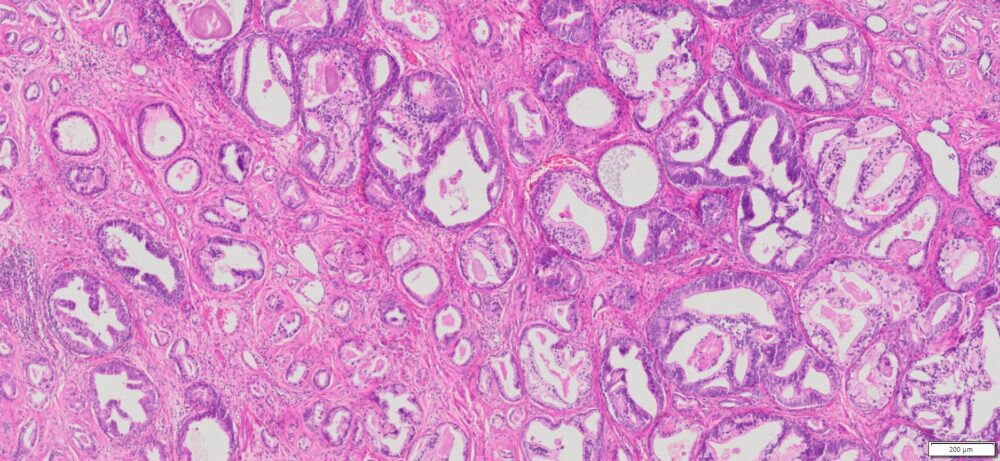

Description

| Tissue | Pathology Diagnosis | Gender/ Age (year) | %Tumor Area | Tumor Grade | TMN/Stage | IHC data |

| Prostate | Human Prostate Adenocarcinoma, Acinar type, Gleason score 9 (4+3) | Male/66 | 31% | II | pT3a, PNx Mx | NA |